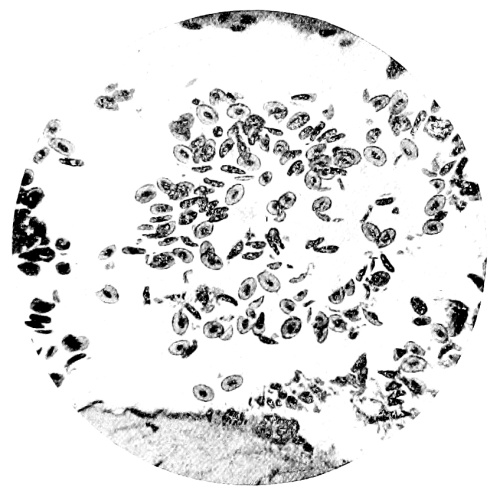

| 9. | Measurement of Blood Corpuscles (sheep) | 97 |

| 10. | Photo-micrograph of Red Blood Corpuscles from Domestic Fowl | 99 |

| 11. | Photo-micrograph of Blood Corpuscles of Fish | 99 |

| 12. | Photo-micrograph of Blood Corpuscles from a Dried Stain of the Blood of a Cod-fish | 100 |

| 13. | Photo-micrograph of a Frog‘s Blood showing oval nucleated Red Corpuscles | 101 |

| 14. | Photo-micrograph of Crystals of Hæmin | 102 |